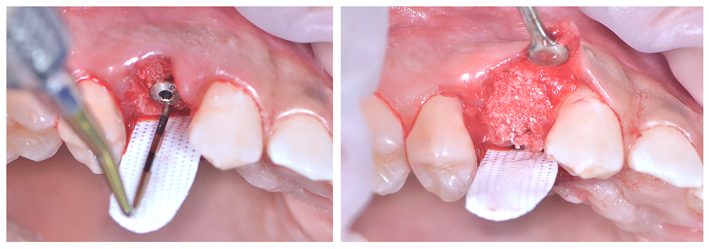

Após o diagnóstico e planejamento, baseados em exames radiográficos e clínicos (Figuras 1 e 2), a primeira etapa foi realizar uma extração dentária atraumática (secção dentária e utilização de periótomo fino e flexível), visando a preservação completa do periodonto de sustentação. Após a curetagem para remoção total da lesão periapical, fez-se a instalação do implante alcançando-se um ótimo travamento inicial e um correto posicionamento ápico/coronal e tridimensional (Figura 3). O Túnel Check, da Implacil De Bortoli (Figura 4), foi utilizado para avaliar o posicionamento tridimensional do implante e selecionar a altura correta do cicatrizador – optou-se por um cicatrizador ao invés do parafuso de cobertura do implante para que não houvesse formação óssea sobre o parafuso, o que tornaria a reabertura muito mais traumática. Após, a membrana Cytoplast TXT 200 Singles (Implacil De Bortoli) foi personalizada e instalada inicialmente na face palatina (Figura 5 – ela não deve ficar tocando nas faces proximais dos dentes vizinhos), seguido do preenchimento alveolar (Figura 6) com substituto ósseo natural contendo 25% de colágeno, o Extra Graft XG-13 (Implacil De Bortoli). Por conter colágeno na sua composição, o Extra Graft XG-13 não fica liberando as partículas ósseas ao longo do processo de osteointegração.

Finalizada a compactação do enxerto ósseo no sítio alveolar (Figura 7), o alvéolo foi selado com a membrana (Figura 7) e realizou-se a sutura com o fio Cytoplast, da Implacil De Bortoli (Figura 9), que é monofilamentar e feito em PTFE (Politetrafluoretileno). Essas características resultam em menor agregação bacteriana e em certa elasticidade do fio, o que reduz a chance de deiscência da sutura, uma vez que ele acompanha o deslocamento do tecido durante a inflamação e aumento de volume. Quatro semanas após a cirurgia, a sutura e a membrana foram removidas (Figuras 10 e 11). Como a membrana não é absorvível, ela deve ser removida entre 21 e 28 dias após a sua instalação. Após o período de 90 dias, realizou-se uma nova tomografia para se avaliar o correto posicionamento tridimensional do implante e a osteointegração (Figura 14).